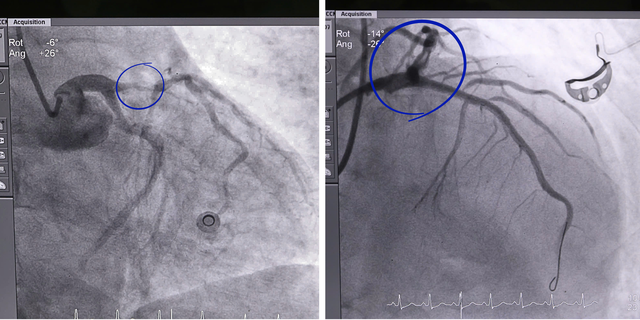

Tình trạng của nam bệnh nhân trước và sau đặt stent tái thông mạch máu.

Ngay sau đó, các bác sĩ tiến hành chụp và xử lý tổn thương động mạch vành, đặt stent tái thông mạch máu nuôi. Đặc biệt, trong quá trình can thiệp, bệnh nhân vẫn tiếp tục có những thời điểm trở nặng, đòi hỏi ê-kíp vừa hồi sức vừa thực hiện kỹ thuật trong điều kiện hết sức căng thẳng.